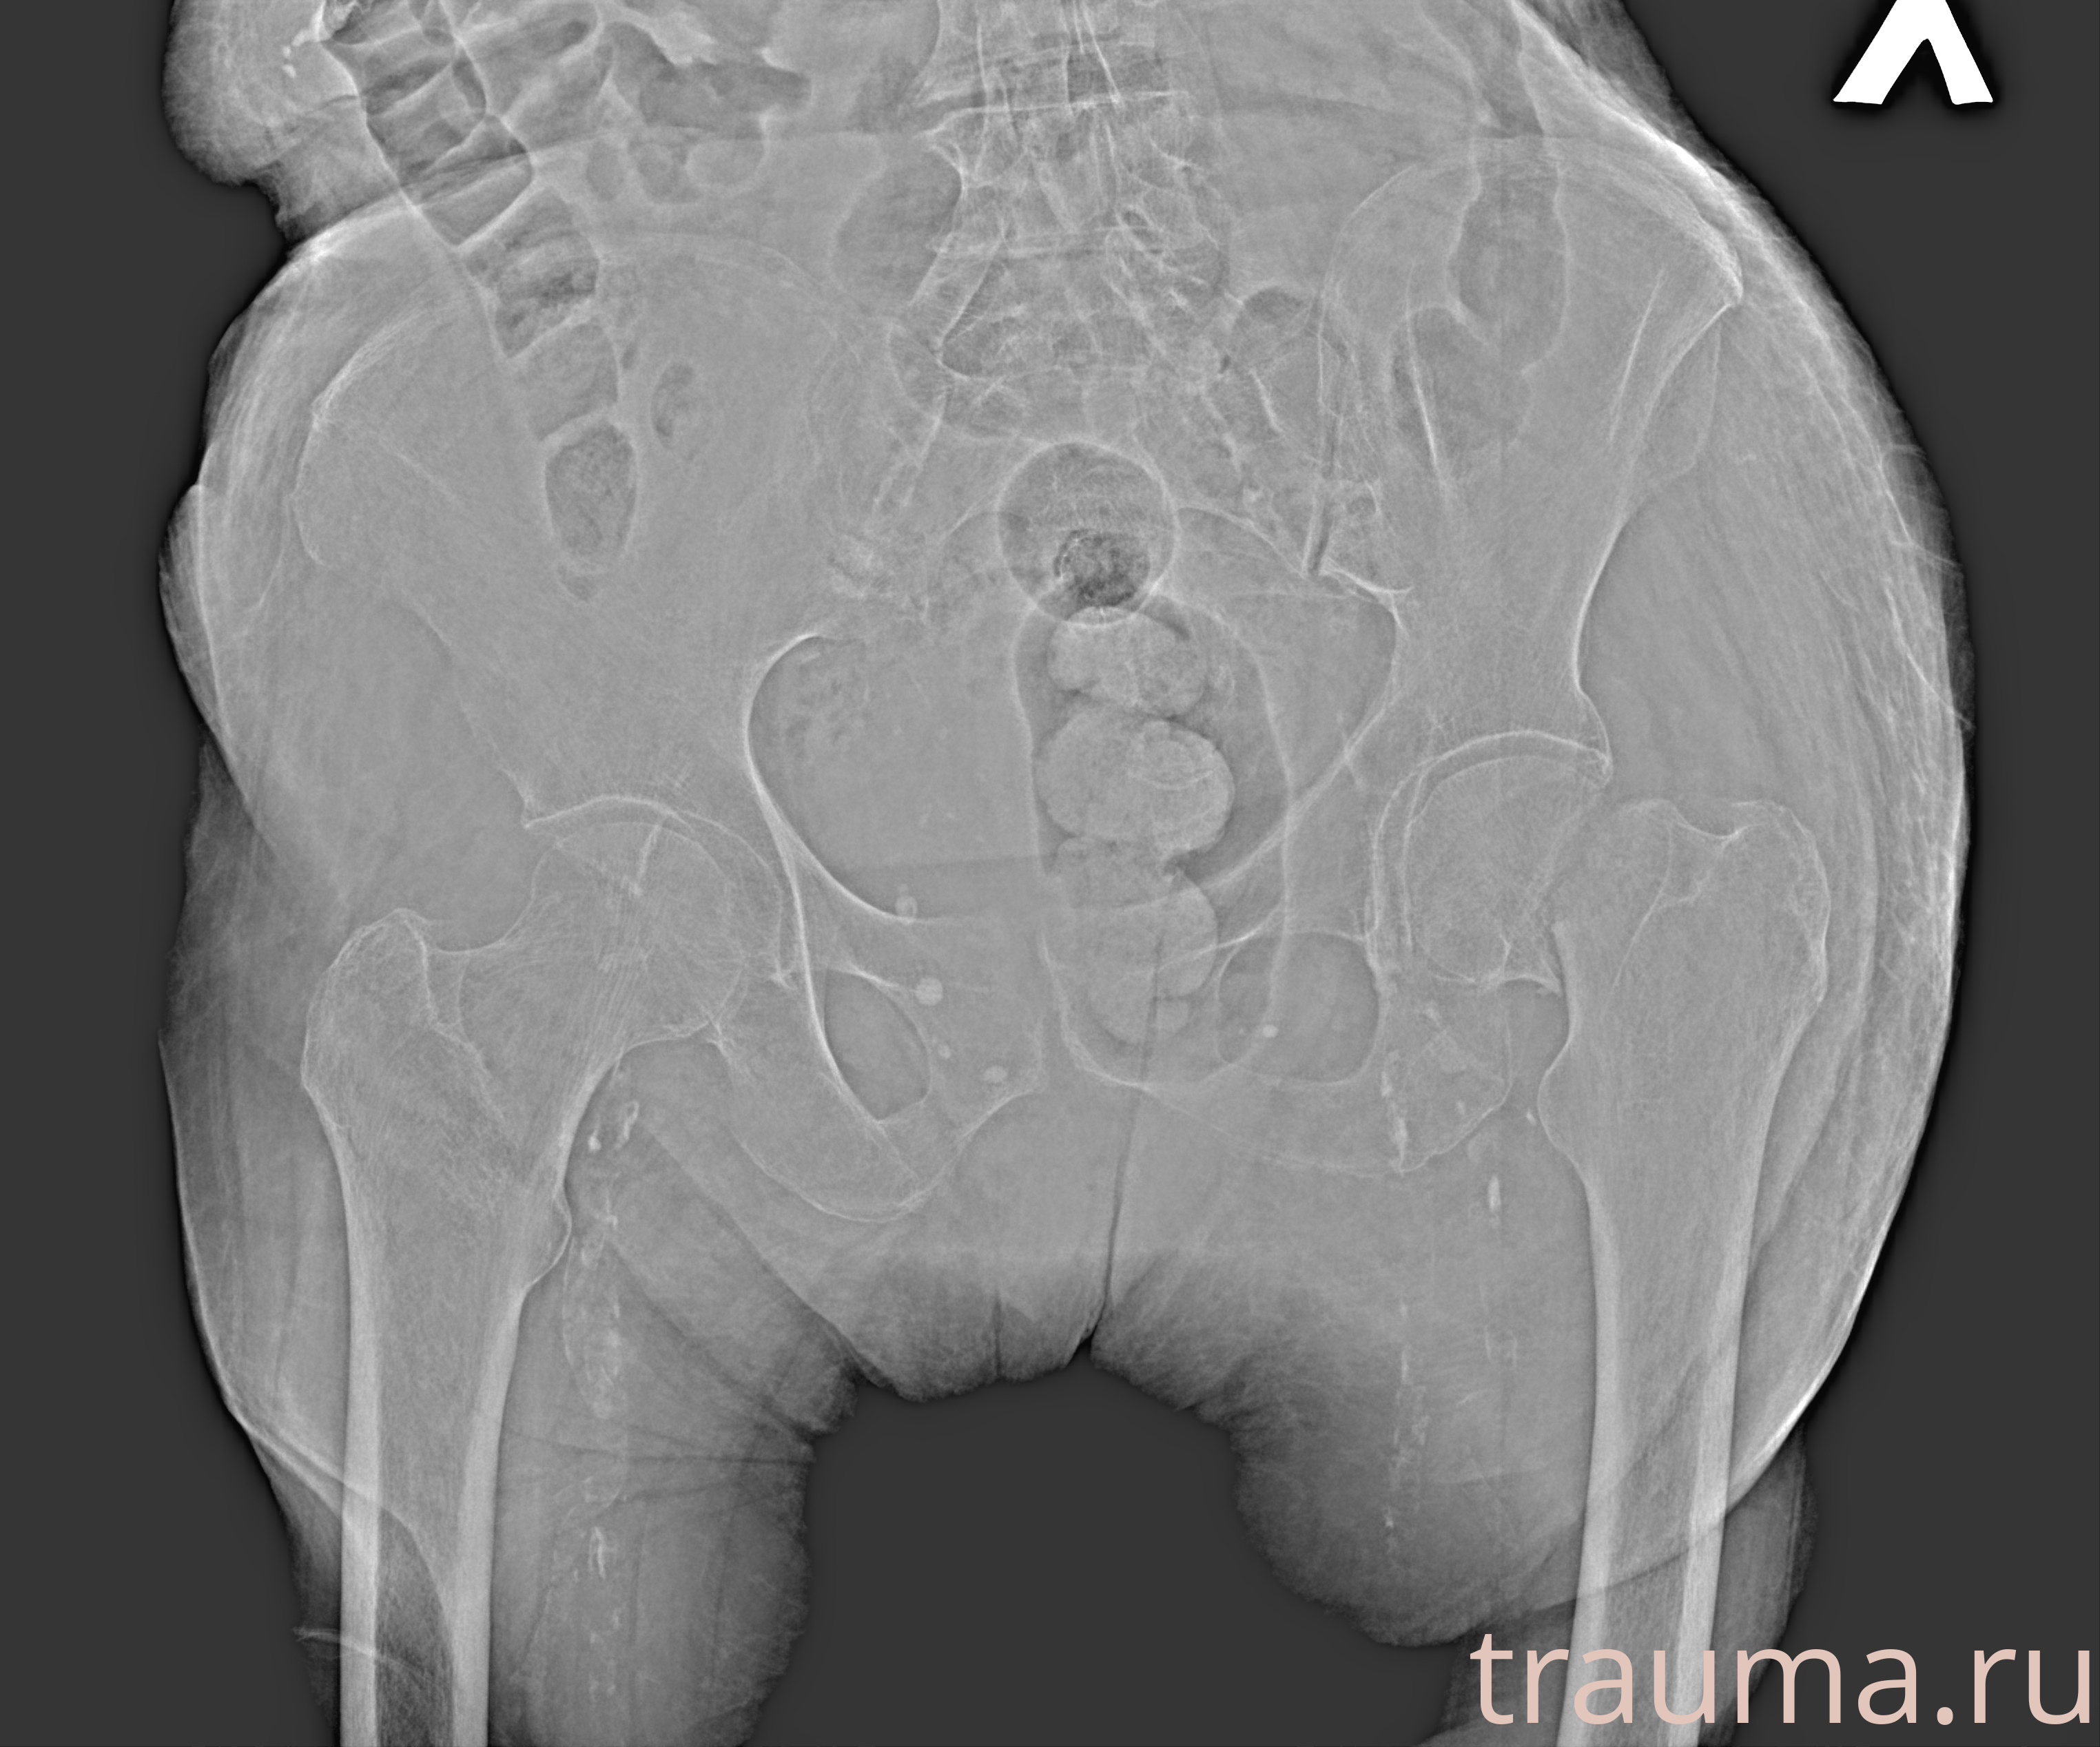

Рентгенограммы

Рентген на дому: по вашему адресу приезжает врач-рентгенолог, травматолог-ортопед с мобильным рентгеновским аппаратом, проводит диагностику травмы или заболевания, делает необходимые рентгенограммы, дает рекомендации по дальнейшему лечению. Получить качественные снимки в домашних условиях возможно благодаря уникальной методике, разработанной МосРентген Центром для института  Склифосовского